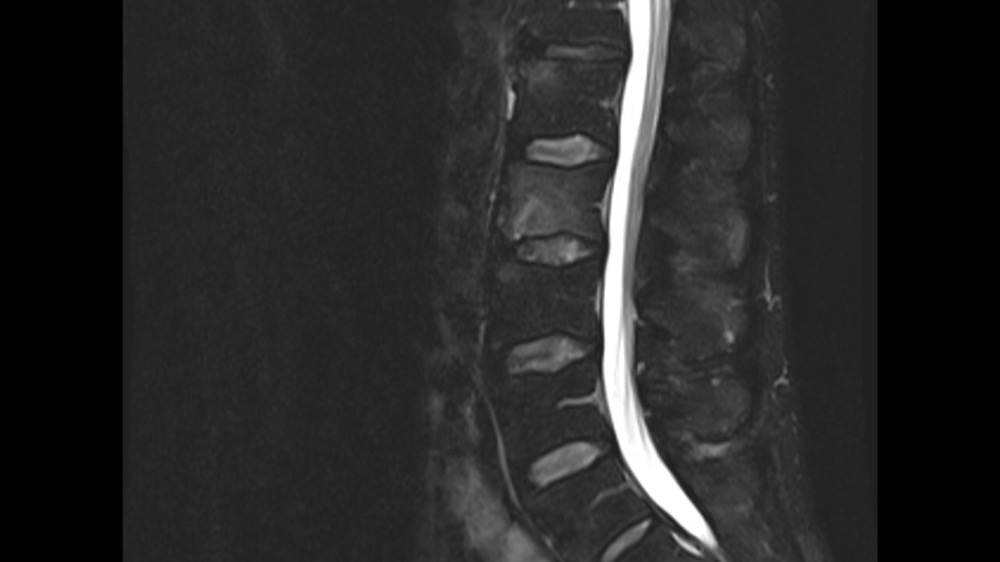

Constance du Boisbaudry 19/01/2022